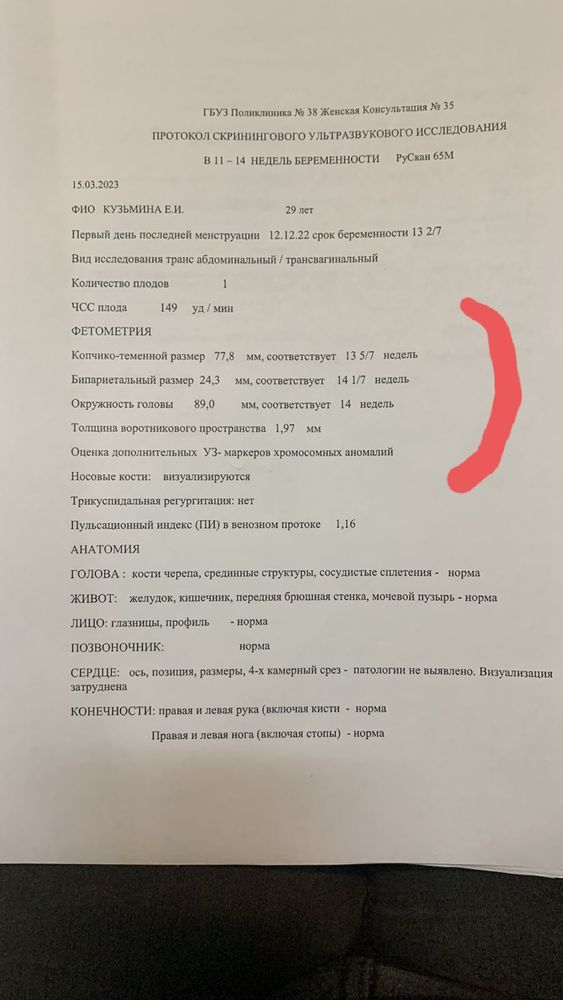

Gennady Babansky, это узи также подтверждает, что менструация была 12.12, срок по ней 9 недель, ребеночек не отстает в развитии от акушерского срока, это прекрасно. КТР также соответствует сроку беременности, тут уже только отталкиваться от срока беременности, тут уже глупо судить о дате зачатия. Но все же это лишний раз подтверждает, что все правильно, зачатие было 25-26 декабря. У вашей девушки явно цикл был всегда 28 дней и овуляция значит происходит на 14 день цикла, и сроки этому соответствуют. А это значит, что овуляция у нее как раз была если месячные 12 декабря, то 26 декабря овуляция, а после овуляции невозможно забеременеть. 1 января это уже 20 день цикла и овуляция уже прошла раннее

Лимоночка, Просто вот тут ещё одно её узи и как-то оно непонятно показывает

Лимоночка, Просто вот тут ещё одно её узи и как-то оно непонятно показывает

Марина, Здравствуйте ПЯ 7,5 мм обнаружили с помощью трансвагинального узи, есть ли разница в узи смотреть через живот и так?

Gennady Babansky, в вашем случае овуляция нормальная была,не поздняя,да и дальше ведь УЗИ делали,там должен был акушерский срок с месячными совпадать

Gennady Babansky, ну вот все совпадает,значит овуляция была на 14 д.ц, соответственно 25 декабря зачатие было,с поздней овуляцией сроки не совпадают,на столько на сколько была поздняя овуляция

Елена Ивановна , ктр соответствует,а остальное оно скачками растет и может и больше и меньше быть,у меня например у старшего окружность головы опережала вообще на 5+ недель,он и родился с большой головой как у трёхмесячного ребенка и после первого скрининга срок обогнял к концу беременности на 2 недели,но он просто крупный был,второй тоже обгонял срок и тоже крупный был,но пдр не меняли,так как крупный не равно зрелый

Елена Ивановна , если б зачатие было 1 января,сроки бы не совпадали с УЗИ,по узи бы срок на неделю меньше был бы,т е там где 9 недель по месячным,по УЗИ бы ктр на 8 недель был,а у вас все по сроку,да и дальше все соответствует,да и тест 11 января 2-3 недели,минимальное значение при котором тест показывает 2-3 это от 120 и выше,до 120 -1-2 ещё показывает,на 10 дпо хгч даже с самой ранней имплатацией не дорастет до таких цифр,у меня с ранней имплатацией -27 всего было на 10 дпо,видела максимум 50 на такое дпо,в вашем случае вообще нет сомнения что зачатие было точно в декабре

Елена Ивановна , аппарат ставит акушерских срок на основе размера эмбриона до 14 недель,дальше уже другие параметры учитывают,но дальше уже по УЗИ может и больше быть и меньше,это индивидуальные особенности,не все же дети одинаковые рождаются,у кого-то крупный плод и будет по узи обгонять срок,у кого-то наооброт маленький и может отставать,а до первого скрининга плод развивается практически одинаково

Вот есть ещё узи от 13 февраля

Вот есть ещё узи от 13 февраля

Марина, то было 13 февраля, а это 15 марта

Марина, то было 13 февраля, а это 15 марта